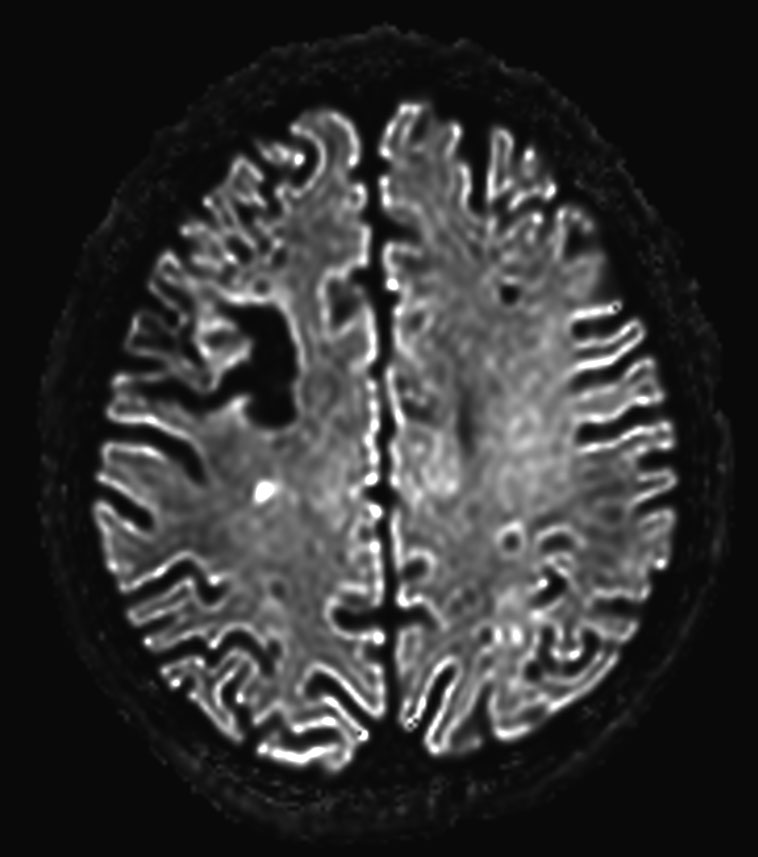

DWI b1000

-

DWI b2000 (computed)